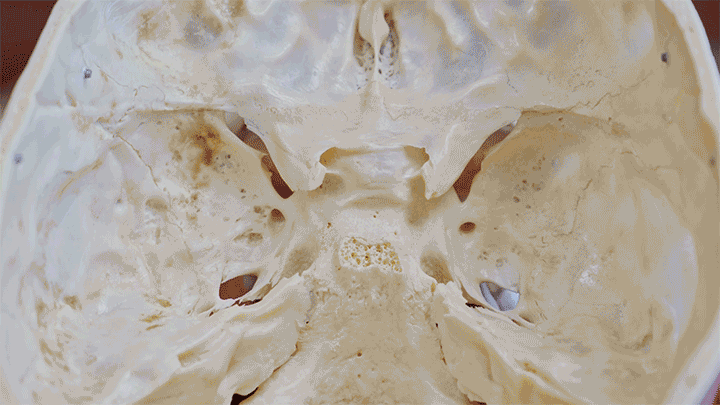

But not all concussions are created equal. Say you slip and fall and hit the back of your head. The back of your skull is hard and smooth, so when your brain hits it, “maybe you’ll see stars, but you’re not going to damage anything,” Knight says. But when your brain bounces forward into the front of your skull, things start to get serious.

The inside of your skull has sharp ridges in the front, above your nasal cavity, Where the smooth back of your skull distributes forces, the sharp features in the front of your skull concentrate them, leading to damage to the frontal lobe.